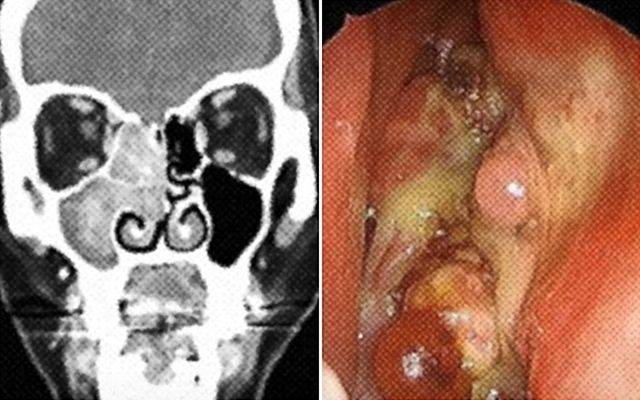

tumor photo. Seoul asan Medical Center

2. Nasal Endoscopy: A thin,flexible tube with a camera is inserted into the nasal passages to visualize the sinuses.

* CT Scan: Provides detailed images of the sinuses.